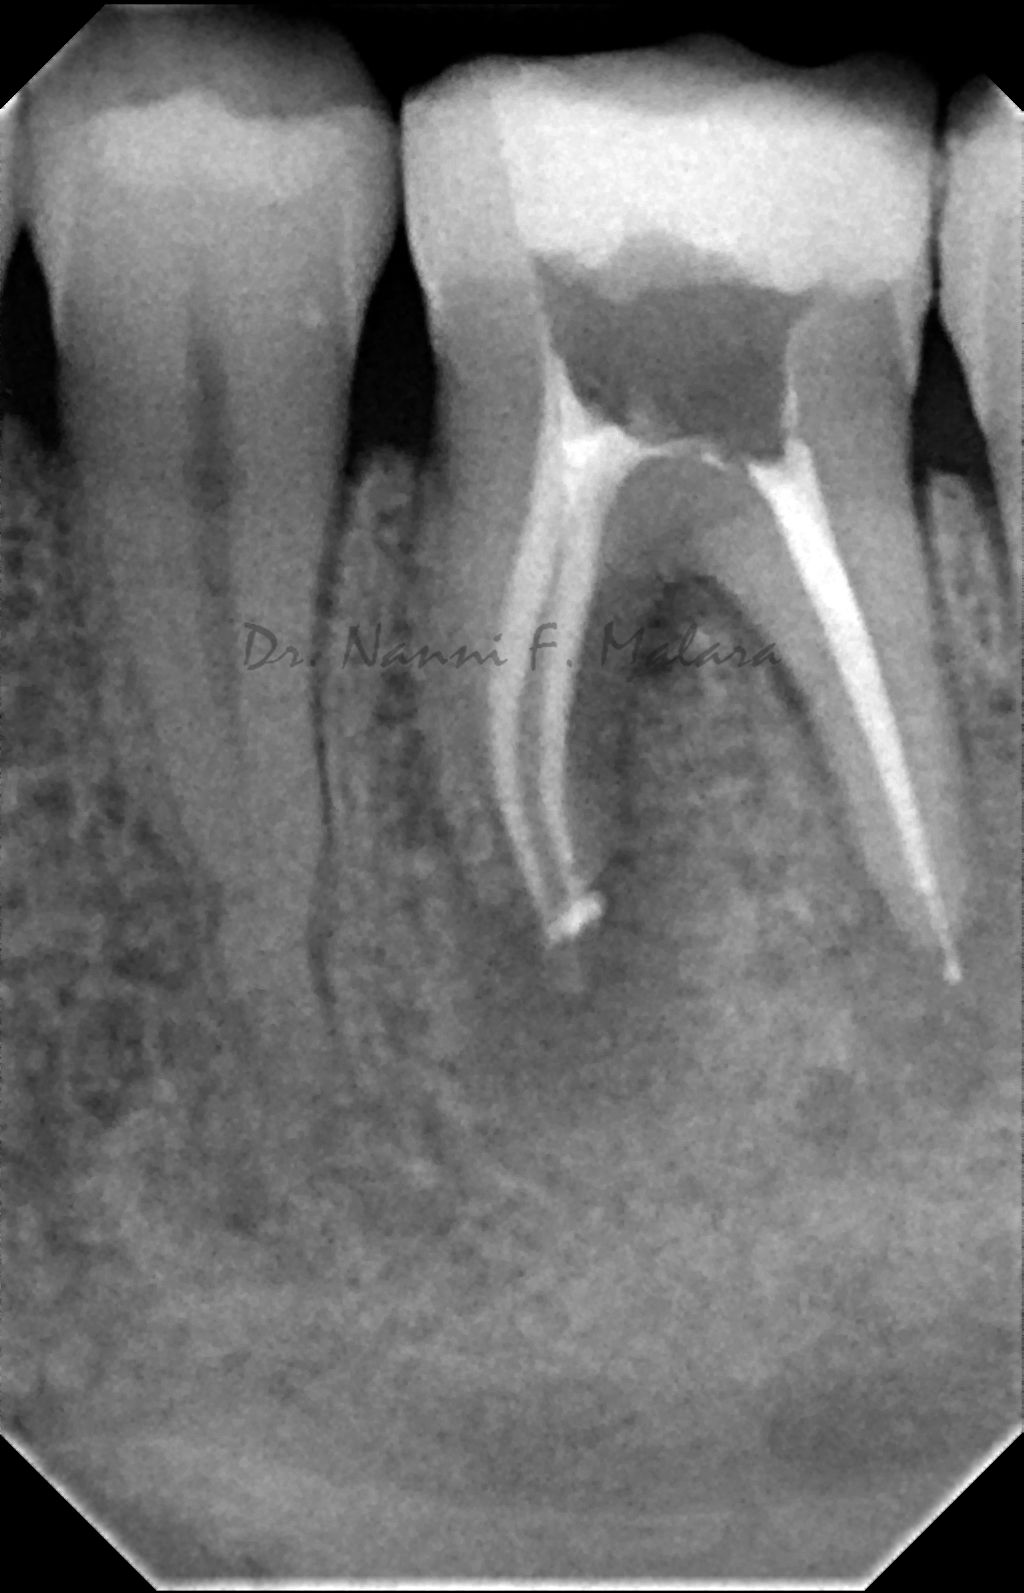

Molare affetto da lesione periapicale a carico di entrambe le radici (Alla radiografia si presentano come aree scure intorno alle radici)

Terapia endodontica con sigillo tridimensionale dei canali radicolari